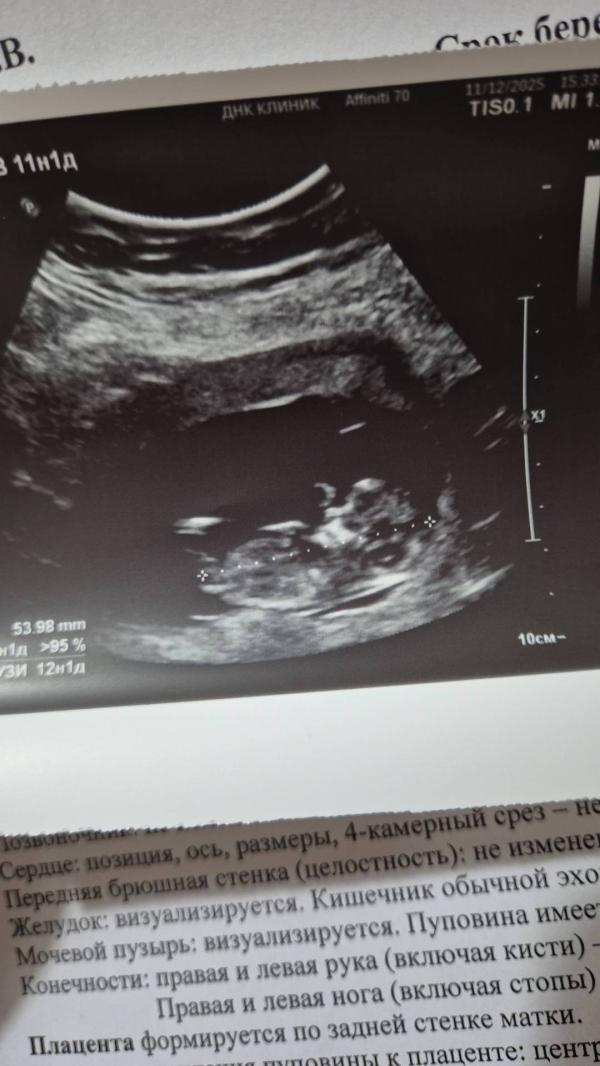

Мой малыш.Узи было внеплановое, муж очень хотел сходить😅На следующей недели предстоит еще скрининг. По месячным 11 н 1 д, по узи 12 н 1 д

На узи предположили мальчика, но я это по анализу уже знала